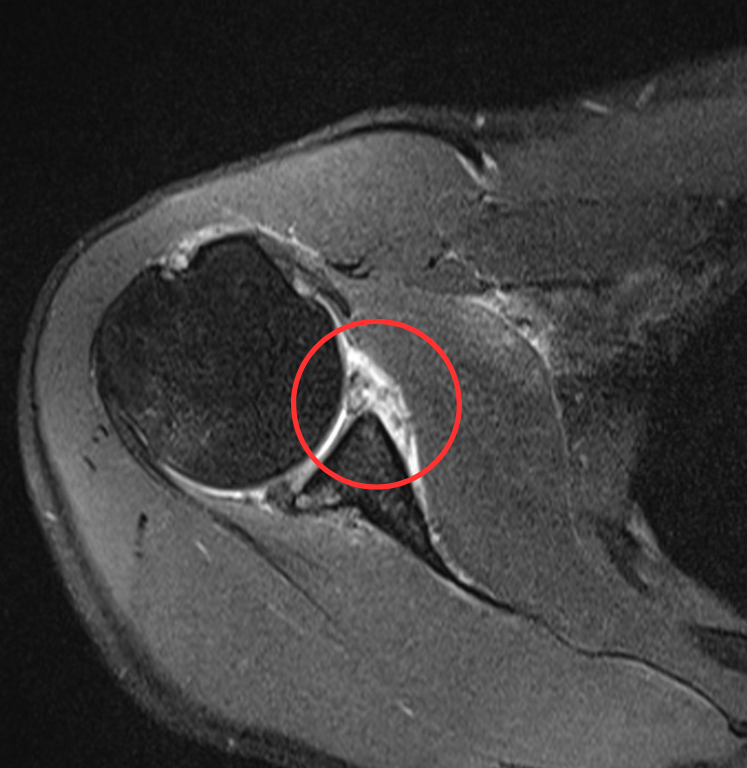

↑上腕骨頭 陥没骨折(Hill-Sachs病変・ヒルサックスびょうへん)

脱臼が繰り返されて骨が陥没してしまいました

この写真の患者さんは、お風呂場で腕を上げただけで脱臼してしまうようになり、手術を実施しました